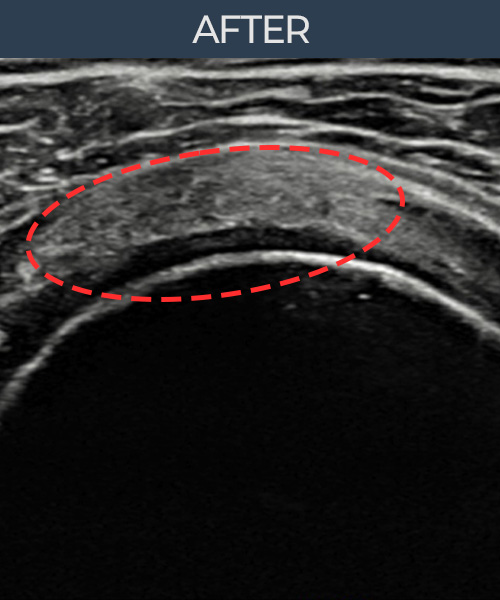

비수술 치료 전후사진

비수술로도 파열된 인대를

물리적으로 재건해 드립니다

플래티넘정형외과에서는 수술없이도 물리적으로

파열된 인대를 재건

하는것이 가능합니다.